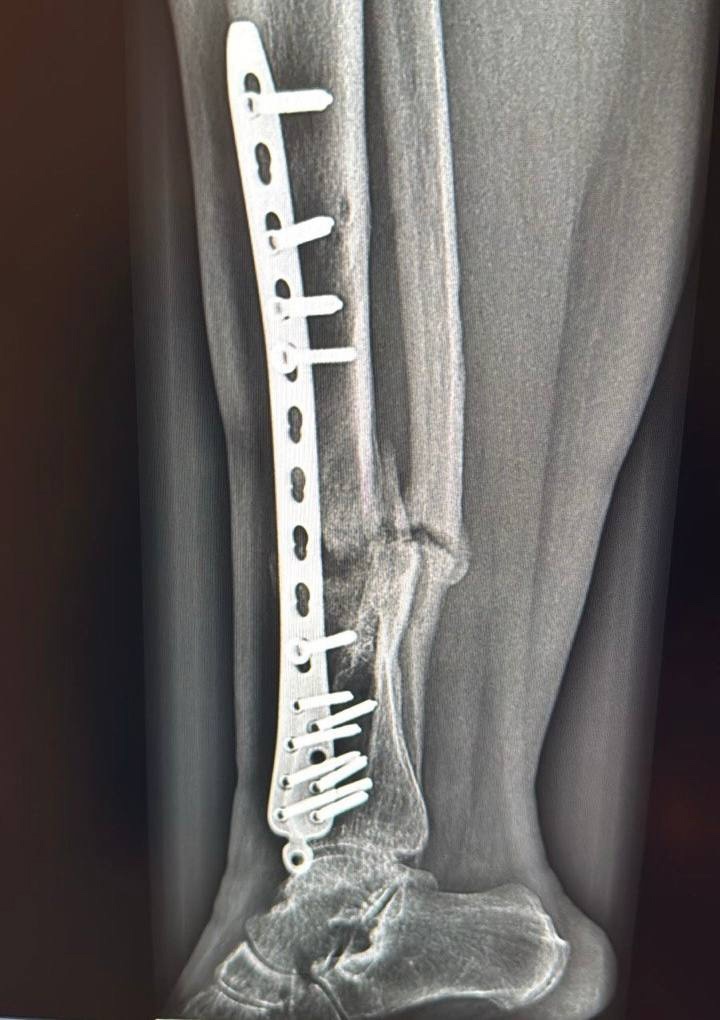

«Сначала мы разобрали кости, которые срослись неправильно. Там была костная мозоль, сформировался ложный сустав, на который нельзя опереться. Пришлось все это разделять, убирать рубцовые измененные ткани, зачищать, накладывать пластину, выполнять костную пластику специальными искусственными трансплантатами», — рассказал ортопед Владимир Росторгуев.

Операция продлилась 4,5 часа. Хирурги также собрали кости на титановую пластину и закрепили на 14 болтов.

Процесс восстановления после операции идет хорошо: женщина перестала чувствовать боль в ноге, которая её беспокоила больше года. По результатам контрольного рентгеновского снимка кость начала срастаться, признаков смещения металлоконструкции нет. Специалисты разрешили пациентке заменить ходунки на палочку, чтобы разрабатывать ногу. Вскоре она сможет ходить самостоятельно.